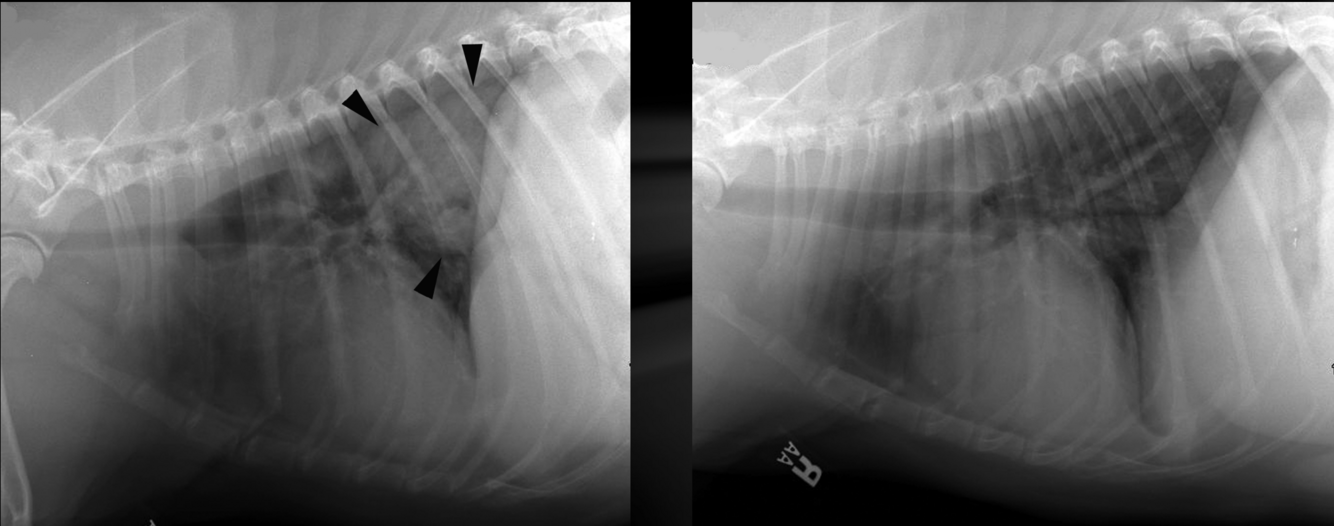

What is shown in these images?

acquired (traumatic) diaphragmatic hernia

-abnormal soft tissue content in thoracic cavity

-no diaphragm outline noted

-shifted gastric axis

-small intestine present within chest cavity and dilated